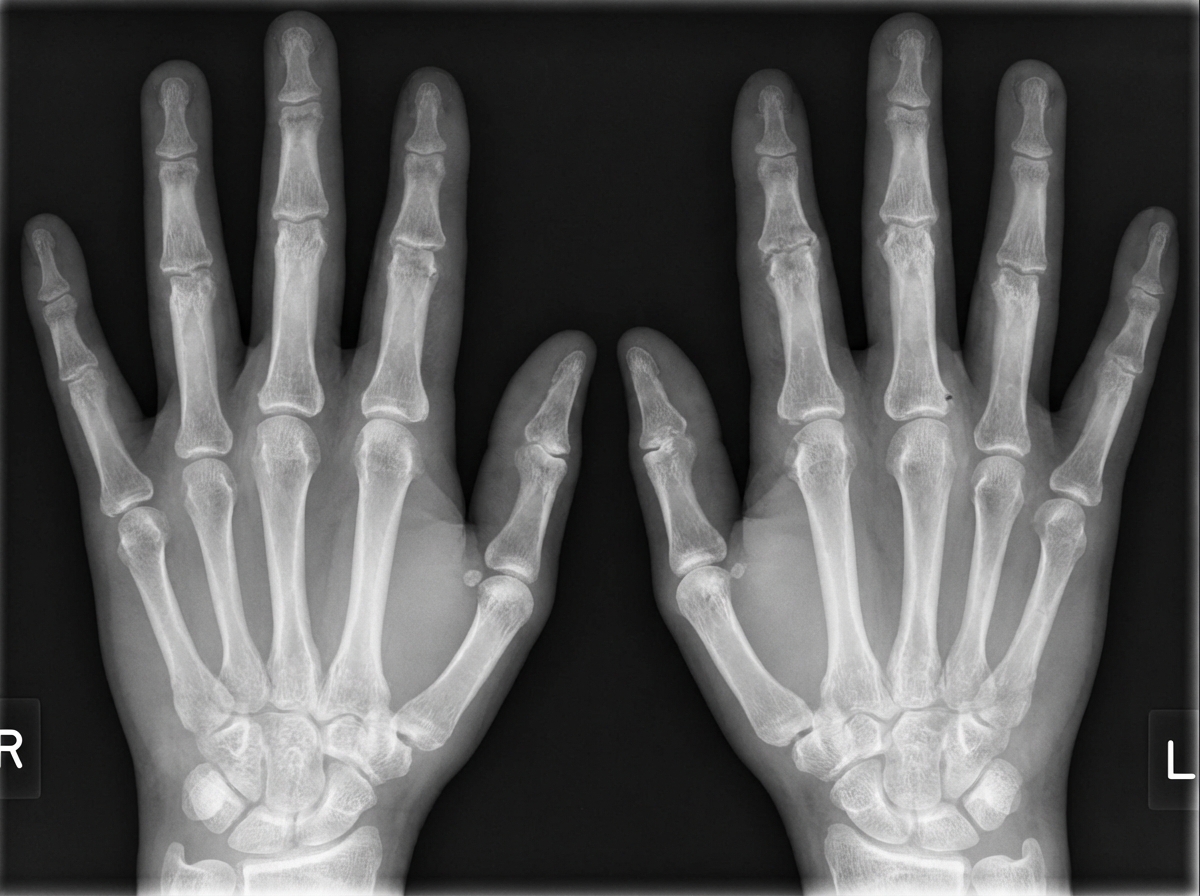

A 40-year-old female presents with a history of fever, weight loss, polyarthralgia, morning stiffness, and bilateral hand pain. Based on the provided radiological findings, what is the most likely diagnosis?

Explanation: ***Rheumatoid arthritis*** - Combination of **systemic symptoms** (fever, weight loss), **morning stiffness**, and **bilateral hand pain** with **polyarthralgia** is classic for RA. - Radiological findings typically show **periarticular osteopenia**, **symmetric joint space narrowing** at **MCP/PIP joints**, and **marginal erosions**. *Osteoarthritis* - Primarily affects **weight-bearing joints** and **DIP joints** with **osteophyte formation** and **joint space narrowing**. - Lacks **systemic symptoms** like fever and weight loss, and morning stiffness is typically brief (<30 minutes). *Gout* - Presents with acute **monoarticular attacks**, commonly affecting the **first MTP joint** (podagra). - Radiological findings show **punched-out erosions** with **overhanging edges** and possible **tophi**, not bilateral hand involvement. *Psoriatic arthritis* - Characterized by **asymmetric joint involvement**, often affecting **DIP joints** with **pencil-in-cup deformity**. - Associated with **psoriatic skin lesions** and **nail changes**, which are not mentioned in this case.